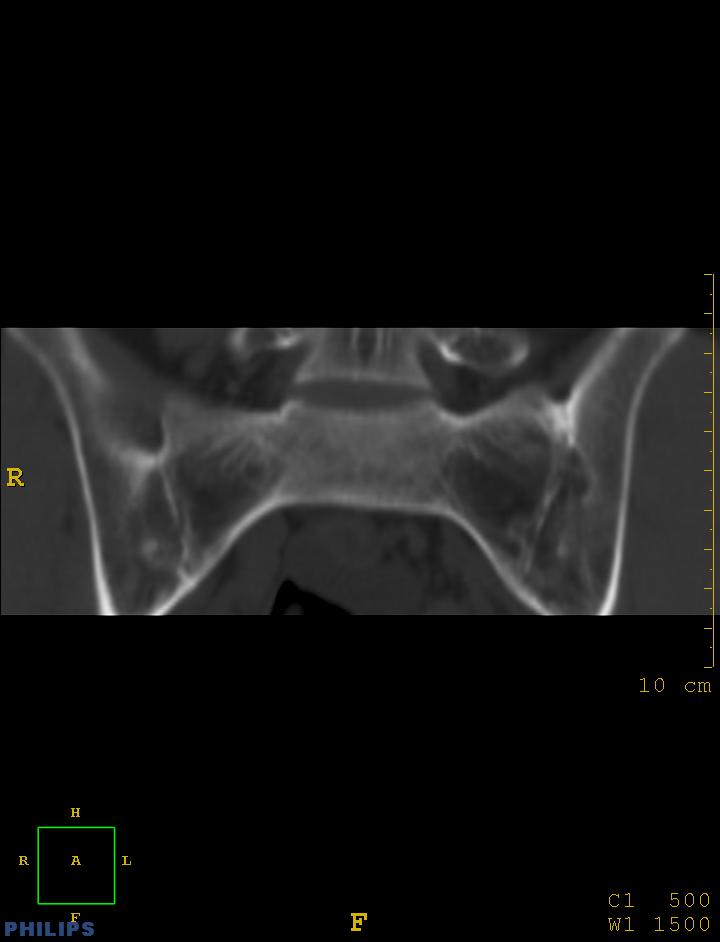

m,34岁,腰痛三年,腰椎活动度明显减低,x片示腰椎竹节样改变

双侧骶髂关节面融合;强直脊柱炎

双侧骶髂关节骨性融合,软骨下囊性变,结合脊柱竹节样改变,典型的强直性脊柱炎。